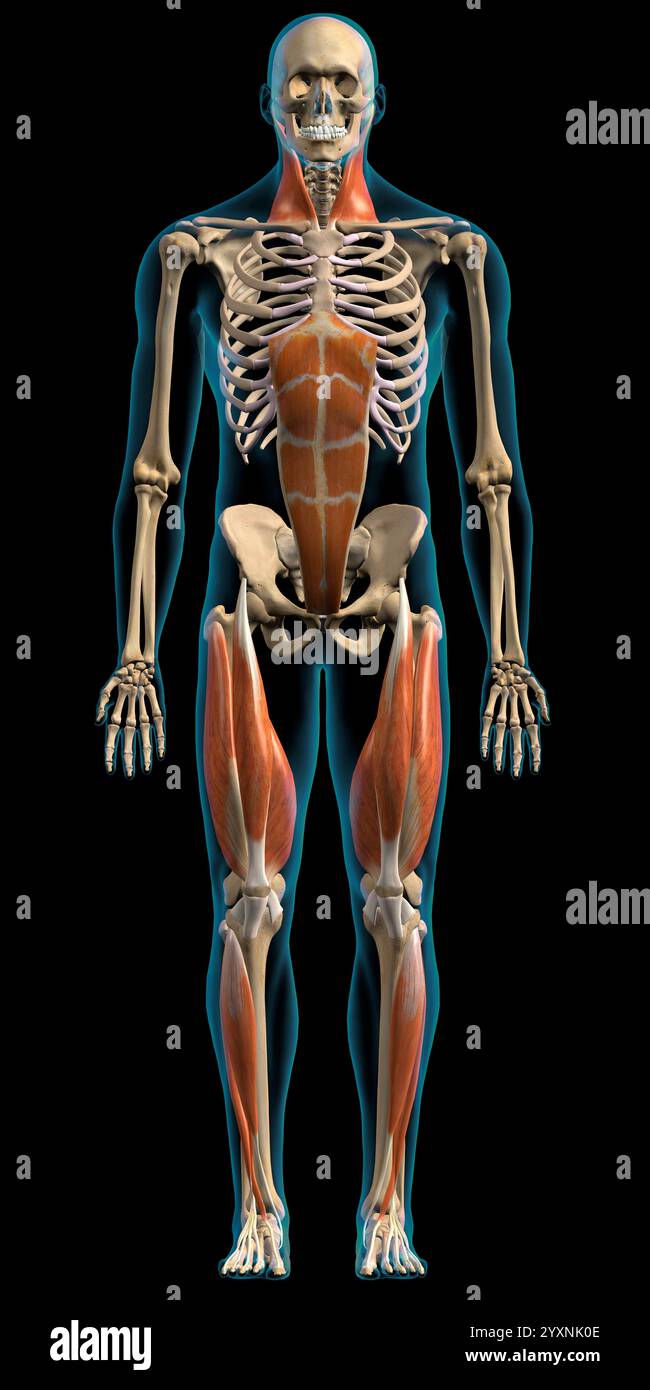

Male superficial network of muscles on white background, frontal view. Stock Photohttps://www.alamy.com/image-license-details/?v=1https://www.alamy.com/male-superficial-network-of-muscles-on-white-background-frontal-view-image636030206.html

Male superficial network of muscles on white background, frontal view. Stock Photohttps://www.alamy.com/image-license-details/?v=1https://www.alamy.com/male-superficial-network-of-muscles-on-white-background-frontal-view-image636030206.htmlRF2YXNK0E–Male superficial network of muscles on white background, frontal view.